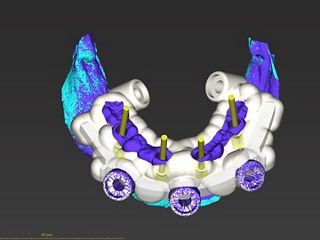

3. Plan of full guided workflow: implant alignment, sleeve placement and surgical drill guide design in coDiagnostiX®.

4. Maintenance of the Occlusal Vertical Dimension (OVD) for immediate restoration by temporary attachment of the positioning bar in occlusion by a stackable guide design (Priamond.de) and using the anchor pins included in the INTEGRAL kit.

5. Using the bar which stays in the mouth, we were able to position the actual drilling guide precisely despite the complete removal of the remaining teeth.